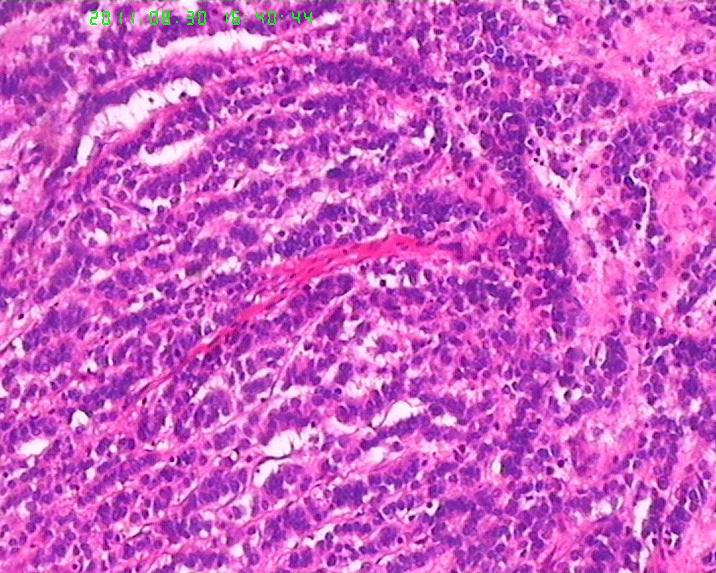

• 焦急:胃肿物,请老师帮看下。图4

图4

肿瘤呈流水线样排列,有腺样结构,核分裂像多见,从这些来说至少不是类癌了,如果是神经内分泌肿瘤,那也应该是神经内分泌癌了,此例可能为腺癌伴神经内分泌分化,需做免疫标记证实是否有神经内分泌分化。

应加做神经内分泌标记物Syn、CgA、CD56和Ki67,小细胞癌/未分化癌不能排除。

本例需要除外神经内分泌癌的可能(比类癌恶性程度高,本例应达到是NET 3级)。